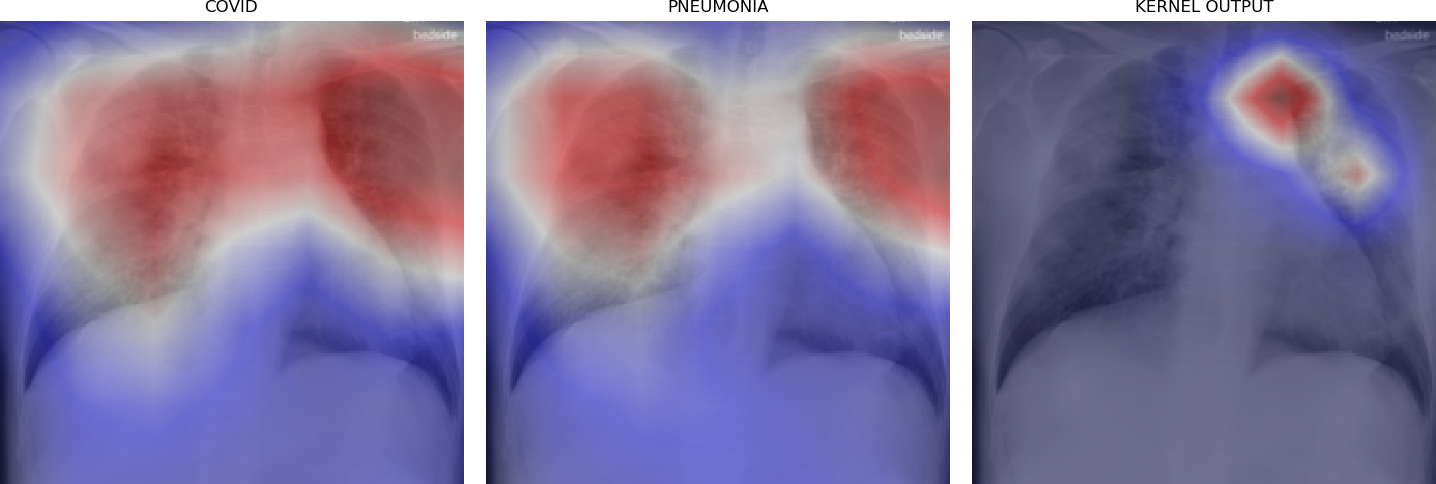

Figure 5 shows triples of X-ray images with superimposed class activation maps for predictions obtained from expert binary models (images one and two) with the third image showing the heat maps computed using our kernel. The intended use of our method is to examine positive classifications from two possibly overlapping classes (i.e. COVID-19, Pneumonia) and extract discriminative features pertaining to the class of interest, i.e. COVID-19. Triples (a)-(f) show positive classifications of COVID-19 and Pneumonia by their respective binary expert models along with class activation maps that localize the image region responsible for that classification. The third image in each triple shows a better localized image region for COVID-19 as computed using our method. Our method is intended to improve explainability of predictions under circumstances where both models return positive classifications resulting in significant overlap in activation maps.

Figure 6 demonstrates the role of the kernel parameter . It controls amplification of the directed differences among the activation maps. Higher values of concentrate the resulting heat map to a smaller region.